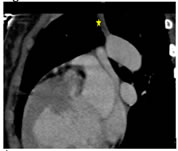

An 8-year-old female child presented with breathlessness with cyanosis and clubbing. The cardiac CT findings are shown below. Van Praagh notation (S,D,S) Figure 9 Figure 10 Figure 11 Figure 9: 1.Pulmonary veins opening into dilated coronary sinus; Figure 10: 1Ostium secundum ASD; Left atrium; Dilated coronary sinus draining into right atrium; Figure 11: Aberrant right subclavian artery

A 21 year old male presented with breathlessness on exertion and bluish discoloration of nails since 1 month. It was a known case of complex cyanotic congenital heart disease. Operated – modified Blalock Tausig shunt. Figure 12 Figure 13 Figure 14 Figure 12: Transposition of great arteries with aorta on right and anterior to pulmonary artery. Right sided aortic arch with mirror branching; Figure 13: Blocked Blalock-Taussig shunt; Figure 14: Double outlet single ventricle